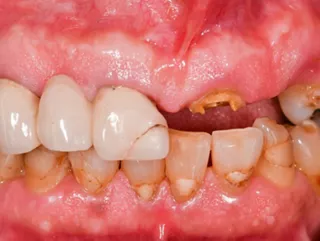

• Situation initiale

• Radiographie préopératoire